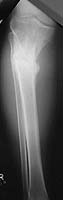

Pt was 10 yrs s/p open tibia fx treated in a cast w/ IR, varus, 2 cm short, and recurvatum. He has done well post op.

preop